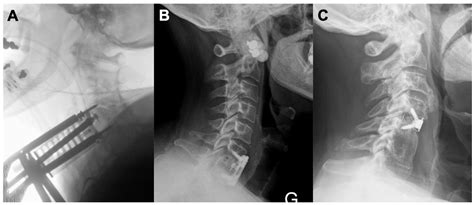

Doctors Debate Whether Cervical Plates Are Truly Necessary For Fusion

Cervical adjacent segment disease: Risks and complications following ...